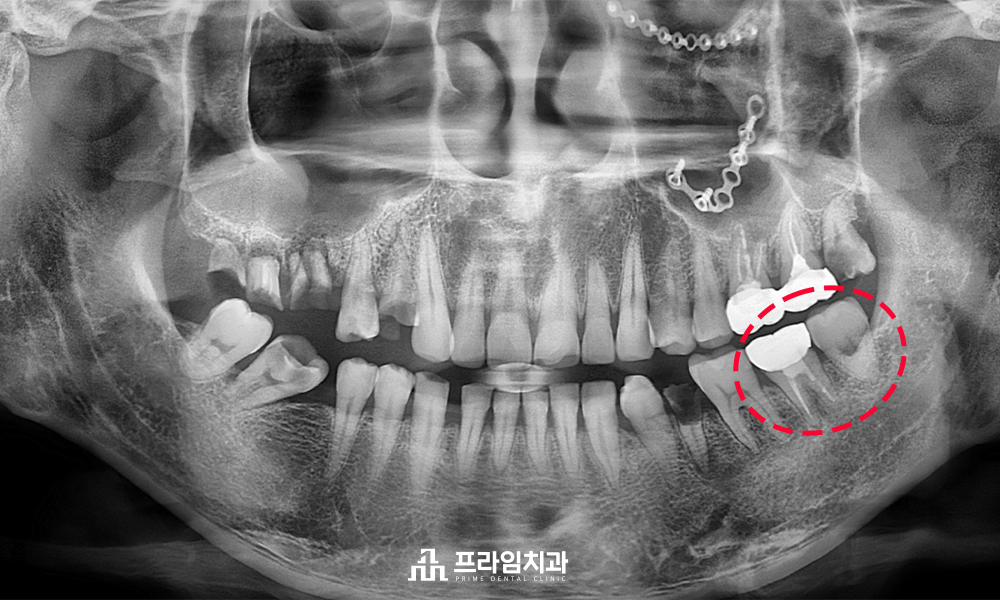

위 분은 타 치과에서

다수의 영구치 발치를

권유 받았다고 하셨습니다.

전반적으로 구강 상태가 좋지 않아

치료할 영구치가 많다 보니,

치료를 진행할 때 발치 개수는 줄이고

살릴 수 있는 치아는 살리기를 원하여

저희 쪽으로 내원했습니다.

뿌리만 남았거나, 충치가 심한 부위는

불가피하게 발치 후 임플란트가 필요했으며

다행스럽게도 왼쪽 아래 어금니 부위는

사랑니가 별 문제 없이 건강하게 존재하는 것을

확인할 수 있었습니다.

.

예후가 좋지 않은 어금니를 발치한 후

사랑니를 그 자리에 이식하는

치아이식술을 진행하기로 치료 계획을 세웠습니다.